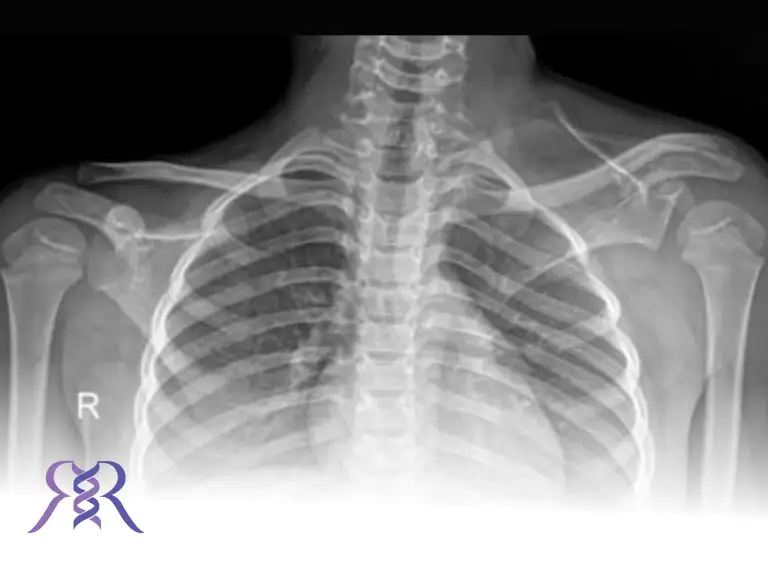

رادیوگرافی ساده (X-Ray): اولین و مهمترین روش برای تأیید تشخیص است. در این تصاویر میتوان موقعیت غیرطبیعی کتف و گاهی باند اوموورتبرال را مشاهده کرد.